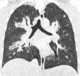

Extensive pulmonary opacity with cavitation

Ground-glass pulmonary opacity

Ill-defined multifocal lung opacities

Multiple cavitary lung lesions

Multiple pulmonary nodules

Solitary irregular cavitary lung lesion

Solitary pulmonary mass

Solitary pulmonary nodule

Solitary sharply-outlined cavitary lung lesion

Thick-walled lung cavity

Thin-walled lung cavity